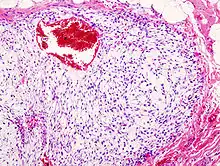

| Histopathologic image of chondrosarcoma of the chest wall. Surgical resection of recurrent mass. H & E stain. | |

Imaging studies – including radiographs ("x-rays"), computerized tomography (CT), and magnetic resonance imaging (MRI) – are often used to make a presumptive diagnosis of chondrosarcoma.[9] However, a definitive diagnosis depends on the identification of malignant cancer cells producing cartilage in a biopsy specimen that has been examined by a pathologist. In a few cases, usually of highly anaplastic tumors, immunohistochemistry (IHC) is required.